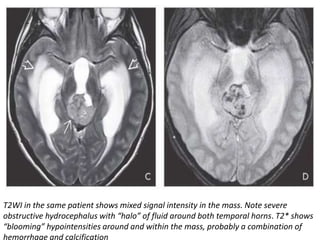

T2WI in the same patient shows mixed signal intensity in the mass. Note severe

obstructive hydrocephalus with “halo” of fluid around both temporal horns. T2* shows

“blooming” hypointensities around and within the mass, probably a combination of

hemorrhage and calcification